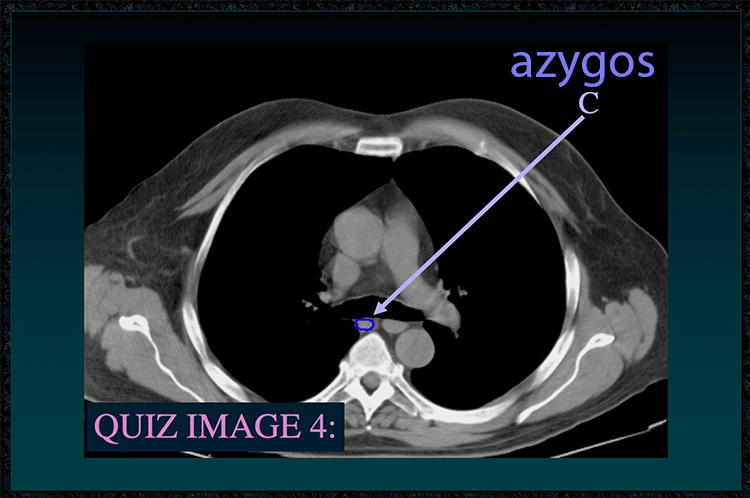

◂Chest Anatomy Review